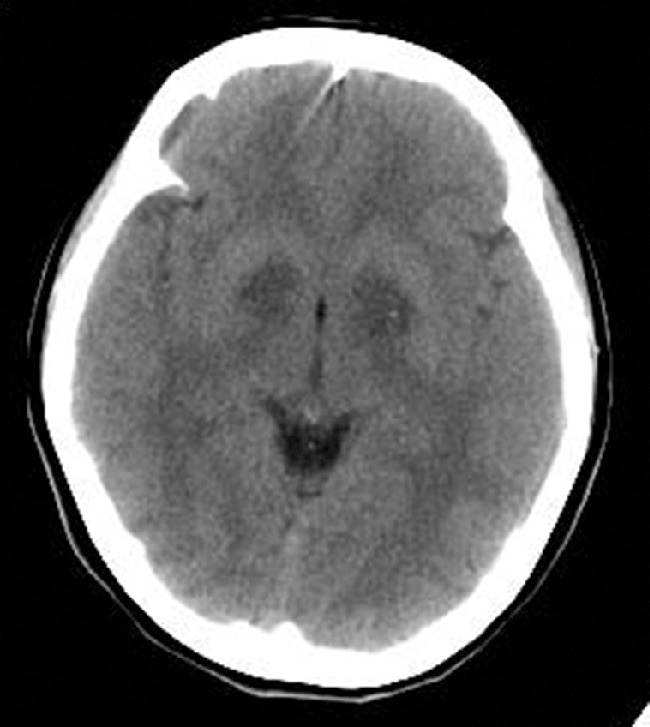

ⅲ) MRIおよびCT (急性期): 急性期には両側の淡蒼球にMRIでは異常信号が,CTでは低吸収域がみられることがある (図1).その他にMRIではレンズ核 (淡蒼球および被殻 (ひかく)) ・淡蒼球以外の基底核 (被殻,尾状核,視床) ・脳室周囲または皮質下の大脳白質・大脳皮質・海馬・小脳などの異常信号や,脳浮腫が認められることもある.